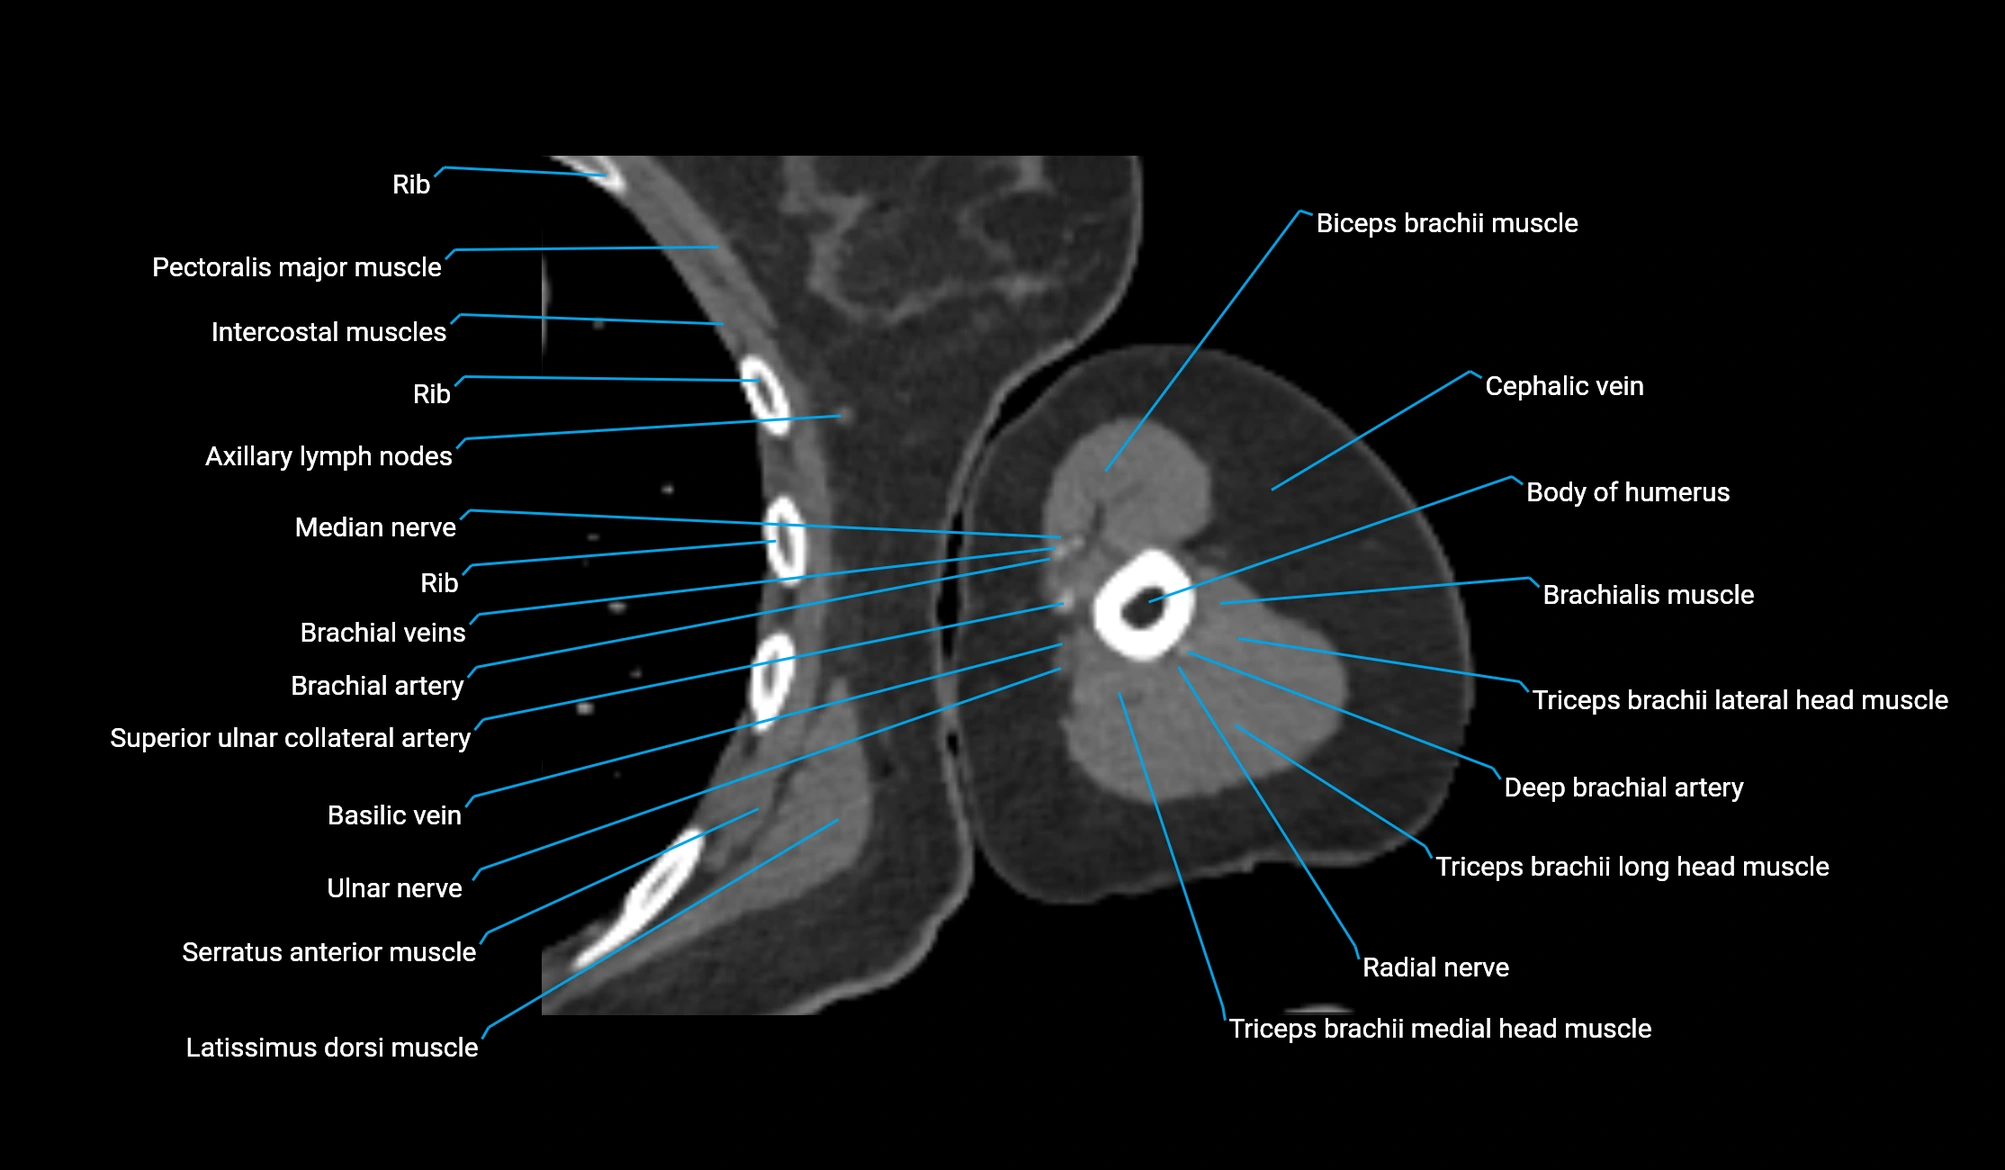

CT image